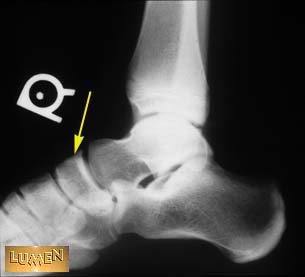

Question: Identify.

Navicular